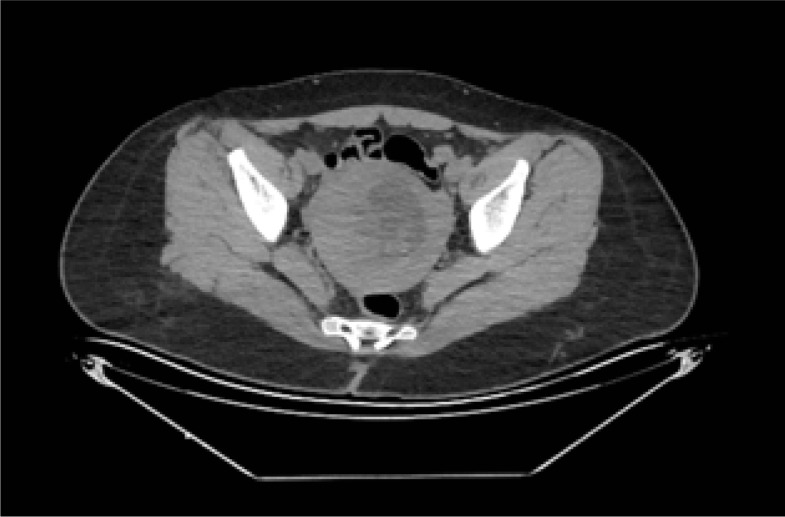

Should routine β-hCG testing be performed before computed tomography scans in women of childbearing age?

育龄妇女应在计算机断层扫描前进行β-hCG常规检测吗?